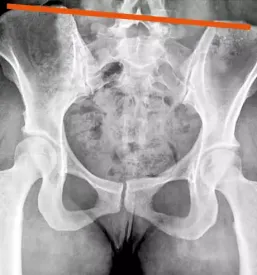

Terapijo za zdravljenje različnih poškodb oziroma težav določimo individualno, zato na obisk pri fizioterapevtu s seboj prinesite tudi svoje izvide. Tako bomo lahko natančno izdelali potek zdravljenja in po končani fizioterapiji s ponovnim pregledom oziroma kontrolo pri vašem zdravniku potrdili uspešnost.